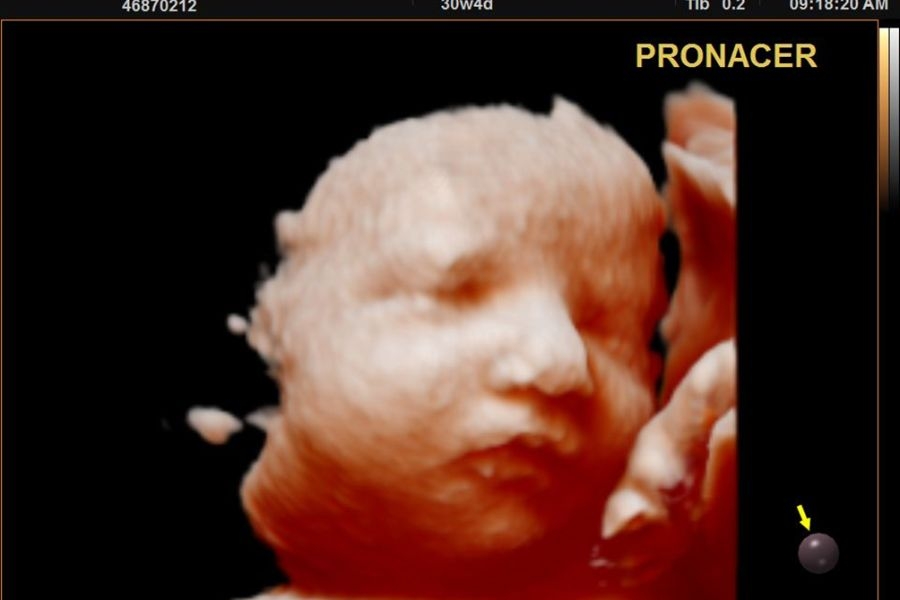

ecografia 4d

Ecografía 4D

Conoce a tu bebe antes de nacer.